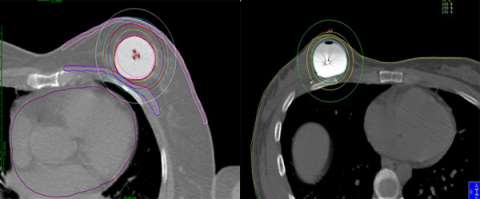

Below is an example of a case here at UCLA where we were able to spare the majority of the implant from receiving unnecessary radiation while achieving optimal coverage around the lumpectomy cavity.

Example of a partial breast case done at UCLA in a woman with breast augmentation who had a SAVI applicator placed. One can see that the distribution of the radiation dose as can be seen in the colored lines is focused around the lumpectomy cavity and that the majority of the implant (light grey) is spared from unnecessary radiation. A different view of the same patient with the SAVI applicator in the lumpectomy cavity just above the implant outlines in yellow.